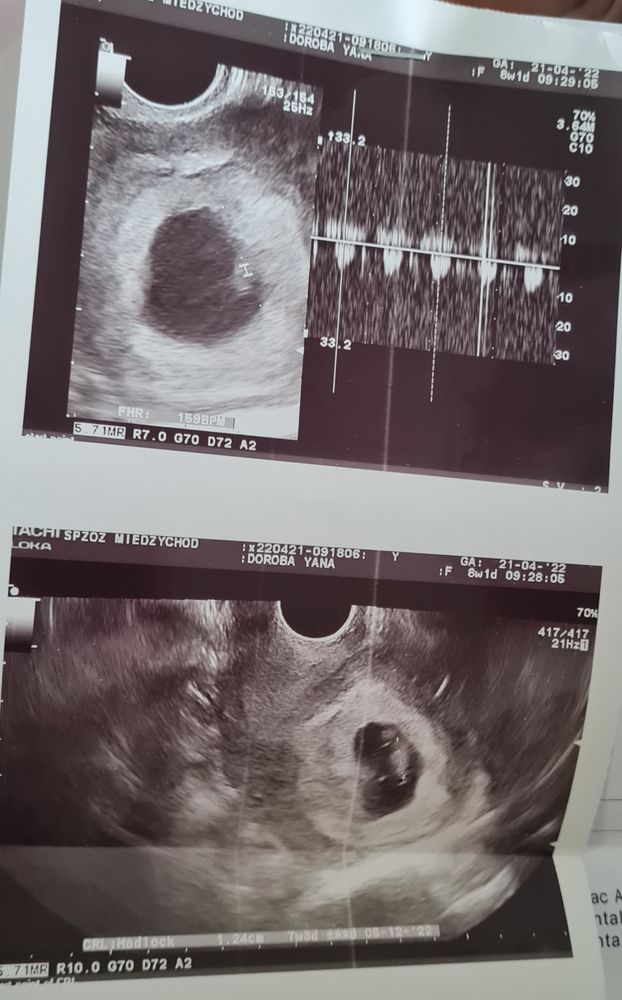

Яна в Благополучная беременность 4 года Первое УЗИ🐣 УЗИ, КТГ, доплер Вот такие мы креветочки🐣🥲 8,1 неделя, сердце 159💗 Посмотрите еще 20 записей на эту тему Лучший ответ Masha Растите здоровенькими 🥰 24.04.2022 Ответить Яна Masha, спасибо большое, вы тоже 🥰 24.04.2022 Ответить Отменить Ответить КТГ.У кого так было ? Отставание по узи на 27 неделе Чаты Беременных Выберите чат: Январята-2026 Февралята-2026 Мартята-2026 Апрелята-2026 Майчата-2026 Июнята-2026 Июлята-2026 Августята-2026